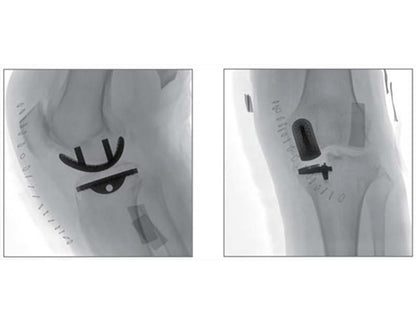

Compared to the conventional 9” image intensifier, a 9” x 9” flat panel detector is able to expand the FoV by 22%, providing more perspective for clinical diagnosis.

Eliminating distorted image caused by electron beam deflection, presenting actual vision of anatomical structure.